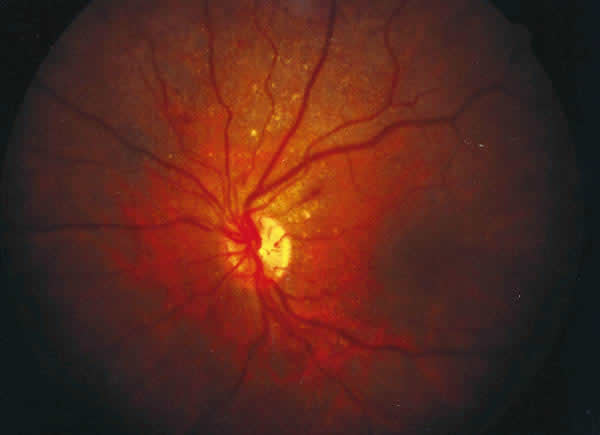

f07-06.jpg (14222 bytes)

Fig. 6.

Caso 2: Retinografía del OD. Se observa la gran dilatación venosa, tortuosidad e interrupciones en el flujo de la rama venosa nasal inferior. Existe edema retiniano de polo posterior, acompañando al cuadro hemorrágico.